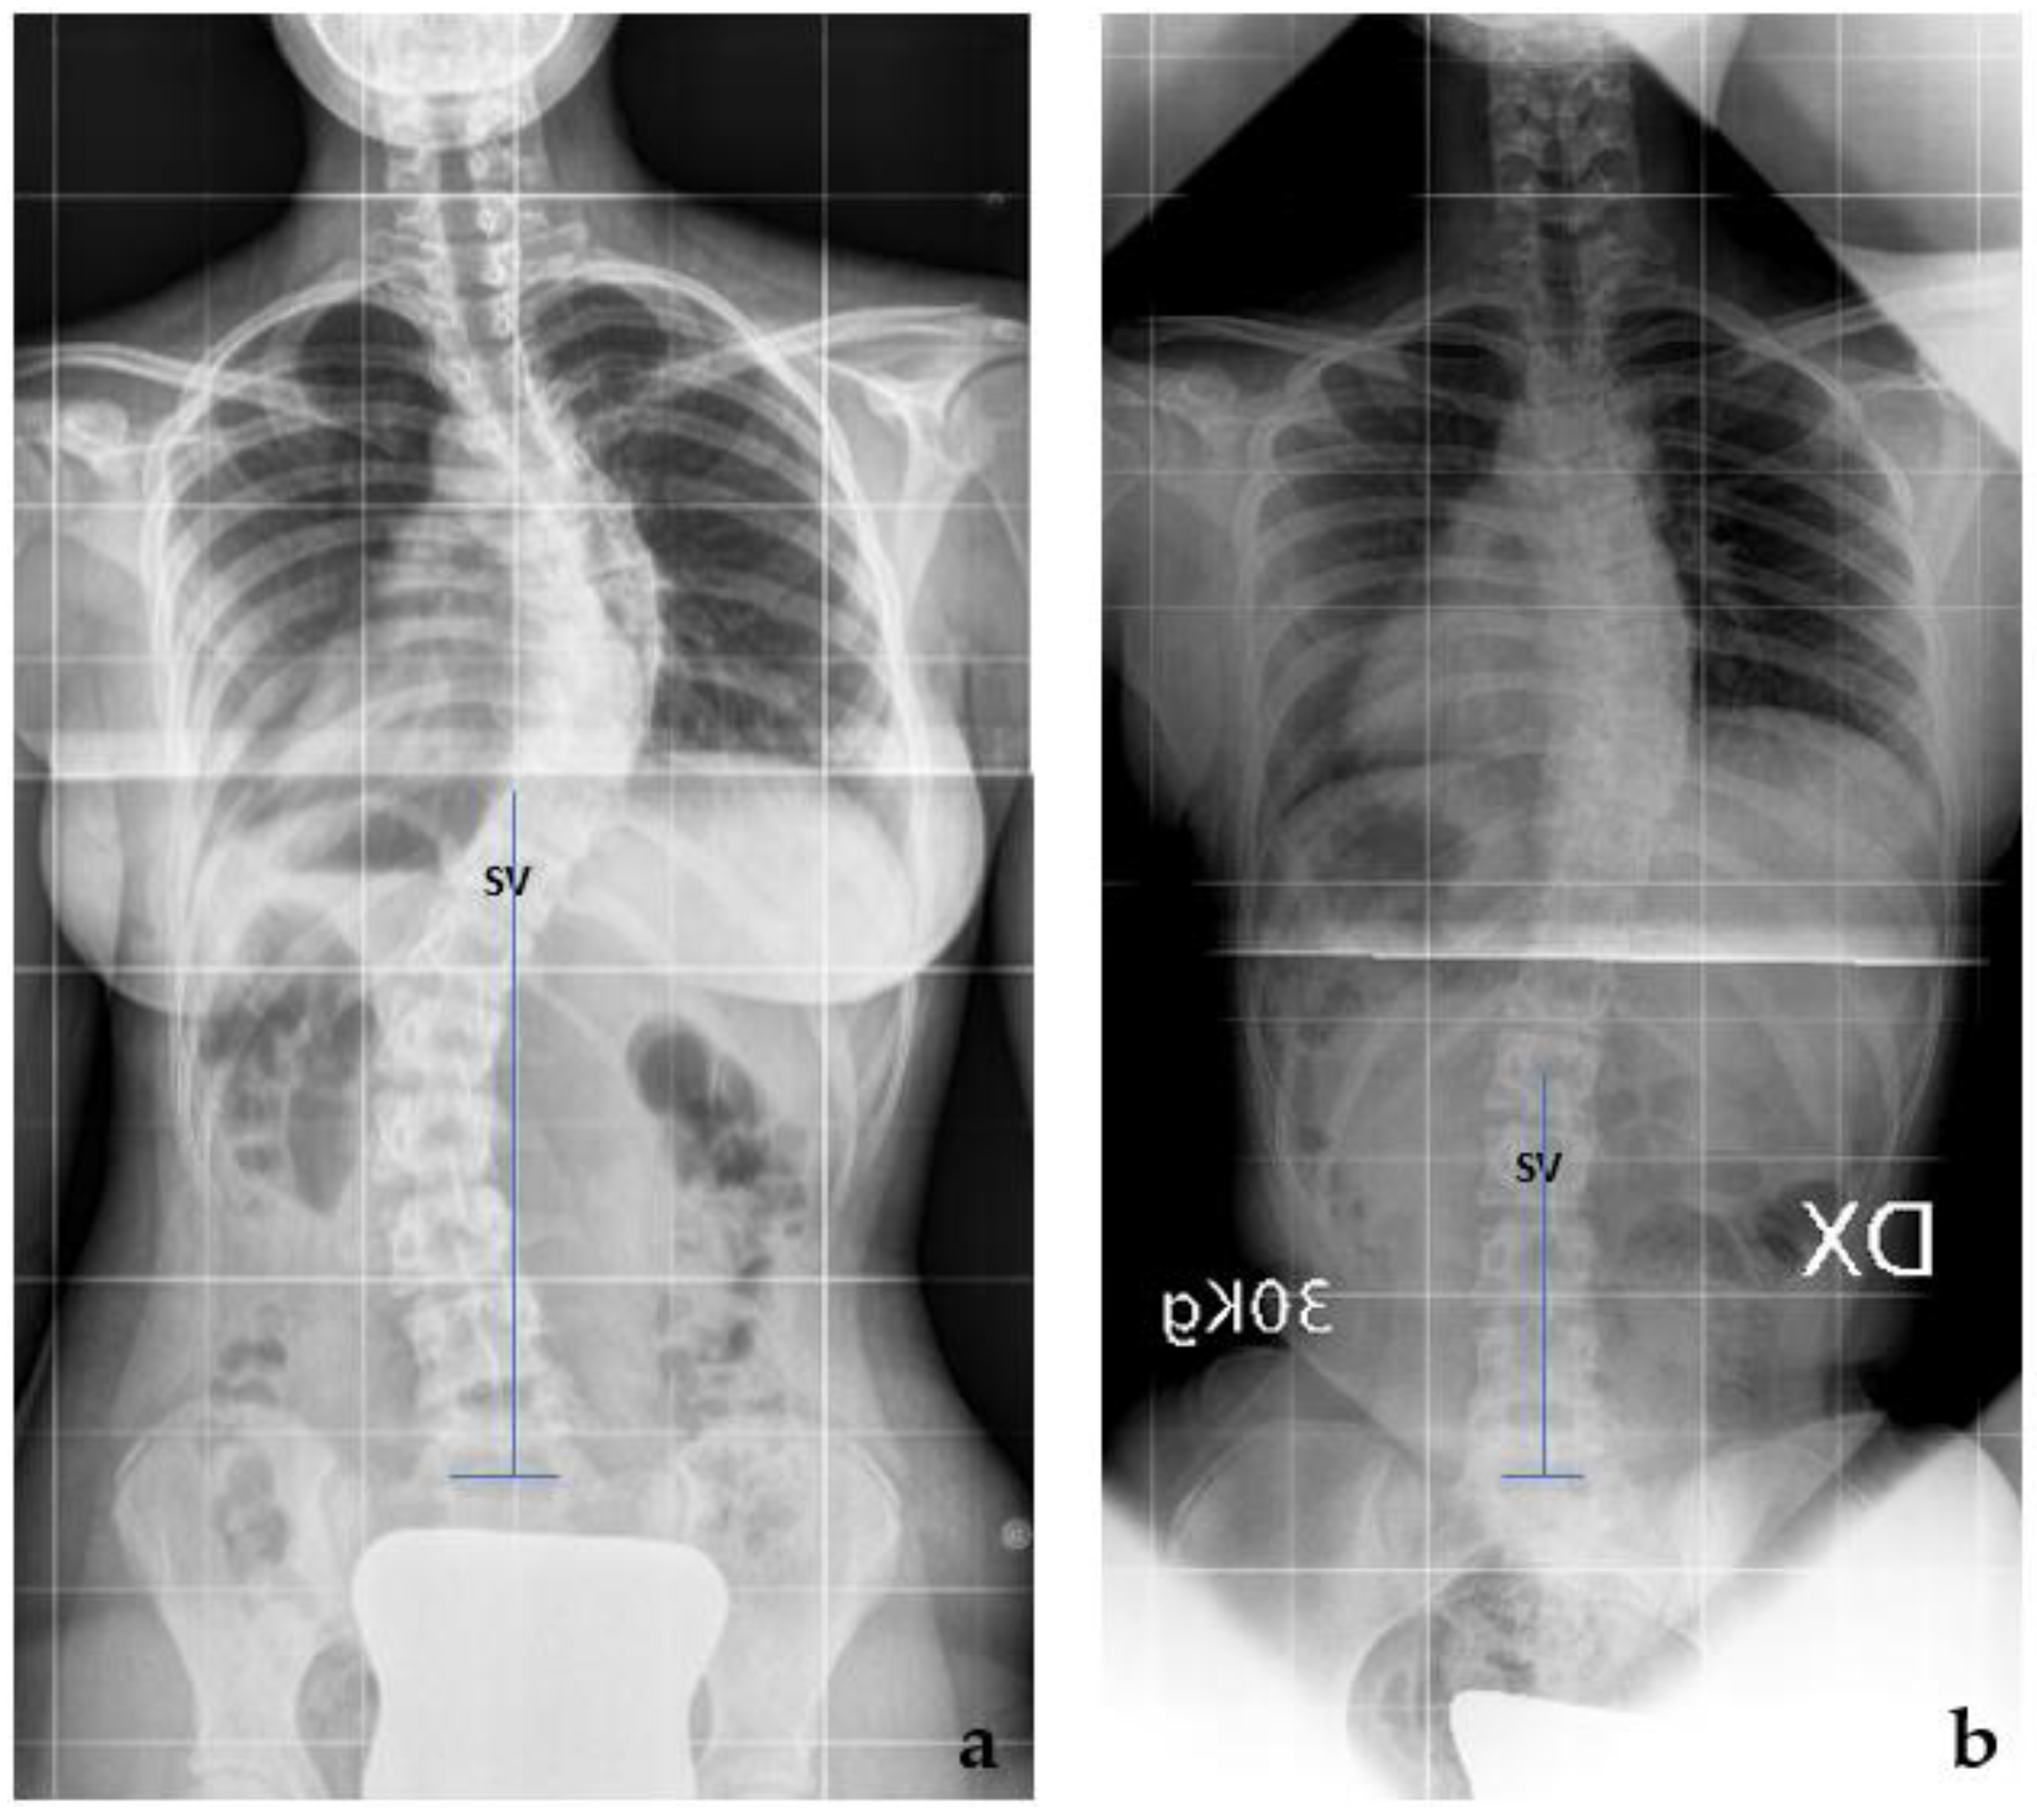

A comparison between the TR and preop X-rays was conducted concerning the gravitational stability of the curve, while the rotational stability was evaluated on the TR, SB, and preop X-rays. The gravitational stability was assessed by evaluating the SV, while the rotational stability was assessed by evaluating the NV. Regarding the gravitational stability, in 23 cases (54.8%), we observed a proximalization of the SV at the TR with respect to the preop X-rays (Figure 2; mean + 2.4 ± 1.2 levels); in 11 cases, we observed no modification of the SV; while in 8 cases, the SV-TE was more distal than the SV-preop. The ‘distalization’ of the SV-TR was observed only in the Lenke 1C curves, (8 out of 16 cases). In those cases with distalization of SV, a significantly greater correction of the Cobb angle of the distal curve was observed both with SB and TR (SB: 62.2 ± 8.8% vs. 49.5 ± 12.9%, p = 0.05, t-test; TR 60.1 ± 6.5% vs. 44.6 ± 10.7%, p = 0.05, t-test) (Figure 3).

Figure 3. Lenke 1C curves: in 8 cases, the SV-TE was more distal than the SV-preop. (a) The SV-preop is T11; (b) the SV-TR is L2.